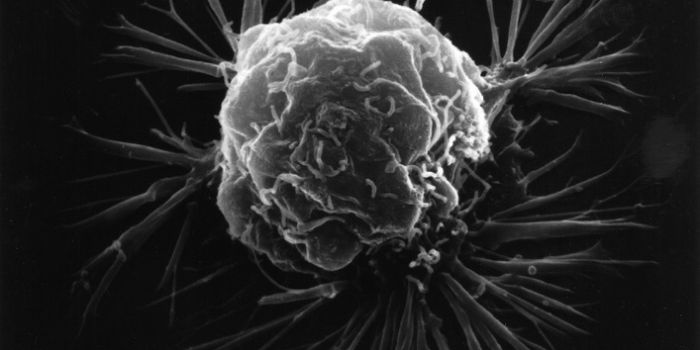

OCT 18, 2017VideosIn 2016, an estimated 246,660 women in the US was diagnosed with breast cancer - a disease that currently ranks as one o ...

OCT 16, 2017VideosScientists have solved the mystery of the connection between high cholesterol levels and increased rates of breast cance ...

OCT 06, 2017VideosOctober is Breast Cancer Awareness Month; however, a recent study shows that many women are not aware of the issue of ov ...

OCT 05, 2017InfographicsCancer touches the lives of most people in the world in one way or another. From family members, friends, or colleagues ...

AUG 31, 2017VideosIn children, brain cancer is the number one cause of cancer-related deaths. Brain tumors are extremely aggressive and of ...

AUG 17, 2017VideosAny cancer diagnosis is daunting, but women diagnosed with Triple Negative Breast Cancer have good reason to worry. It's ...

AUG 10, 2017VideosOn the whole, rates of breast cancer cases are decreasing. However, for certain ethnic groups, the rates have been on a ...